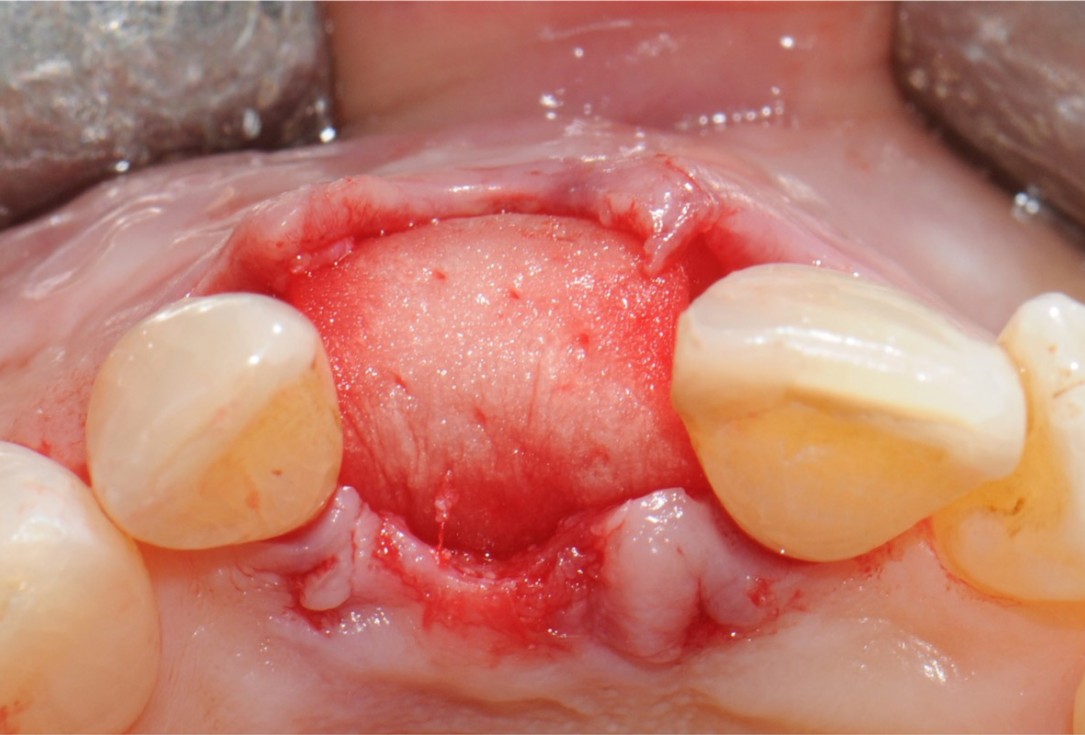

8/18 - Application of mucoderm® that is cut into shapeTooth extraction and socket sealing with mucoderm® - Dr. A. Rossi